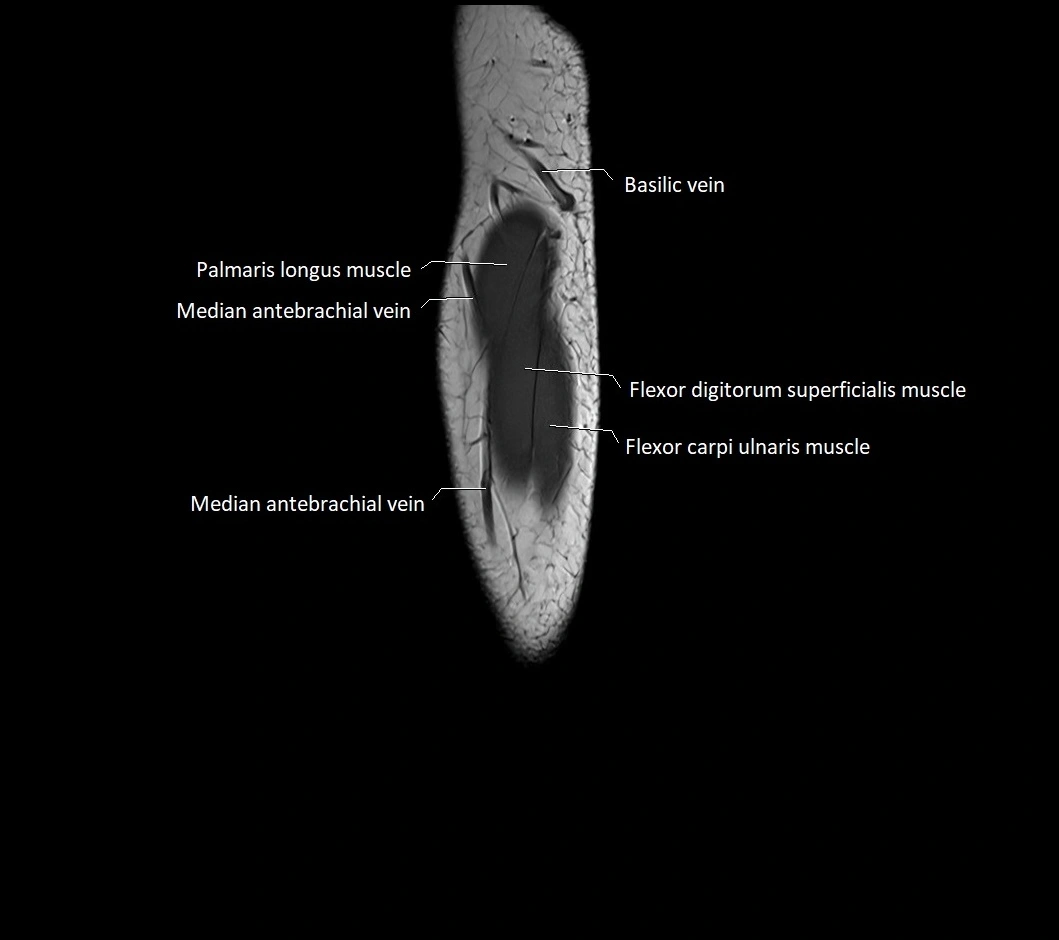

MRI images

image